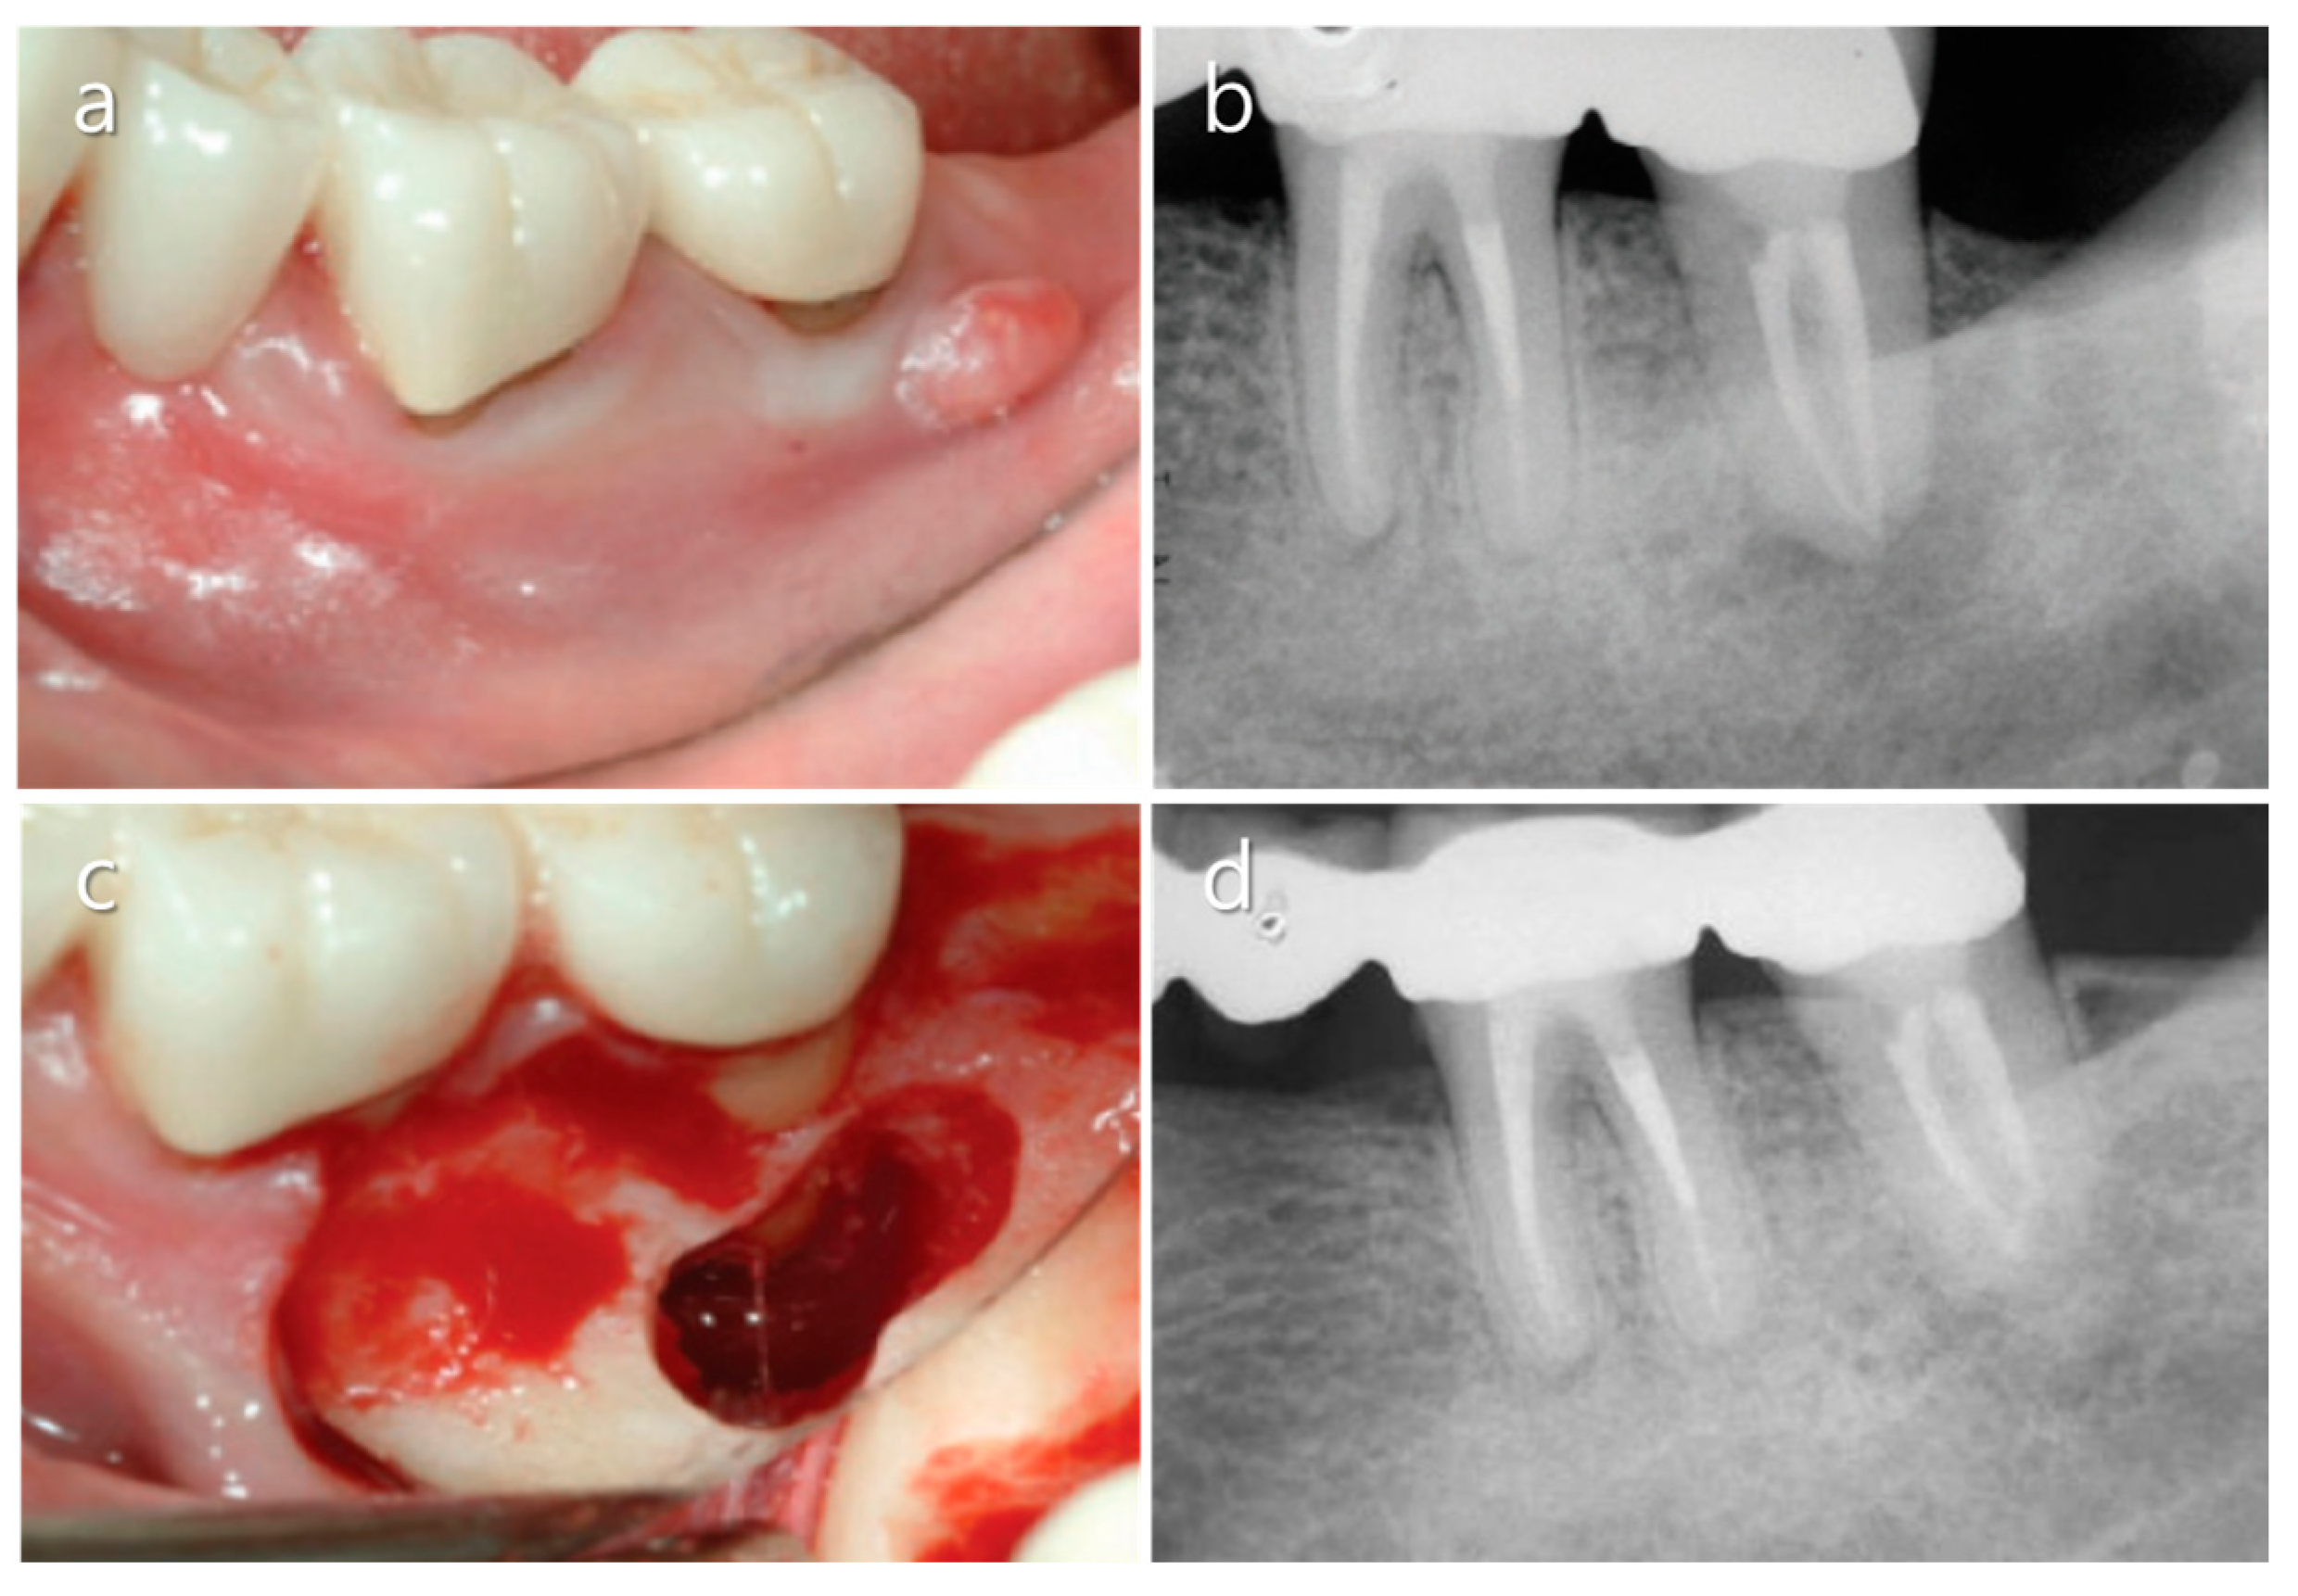

3.1. Flap Design

3.2. Osteotomy